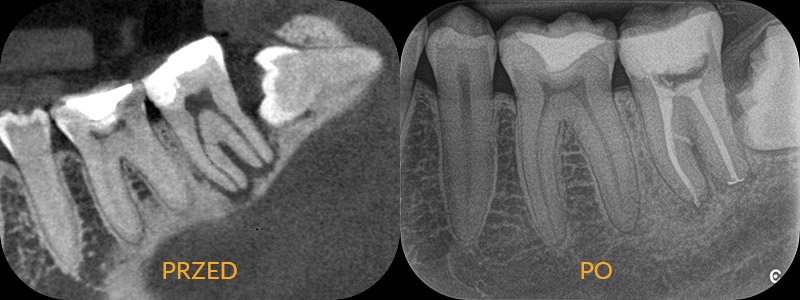

Pacjent zgłasza się ze złamaną ścianą zęba. Chce jak najszybciej odbudować nadłamaną część. 15 lat temu ząb był leczony kanałowo. Kontrolne zdjęcie wykazuje nieprawidłowo wypełnione kanały korzenia, wypełnienie jest nieszczelne, pojawiła się też rozległa próchnica. Lekarz nie może podjąć się odbudowy zęba, bez wcześniejszego powtórnego leczenia kanałowego. Usuwa stary materiał, opracowuje kanały na nowo, wypełniając je na koniec ciepłą gutaperką. W związku z rozległym uszkodzeniem korony zęba zostaje zaplanowana odbudowa protetyczna.